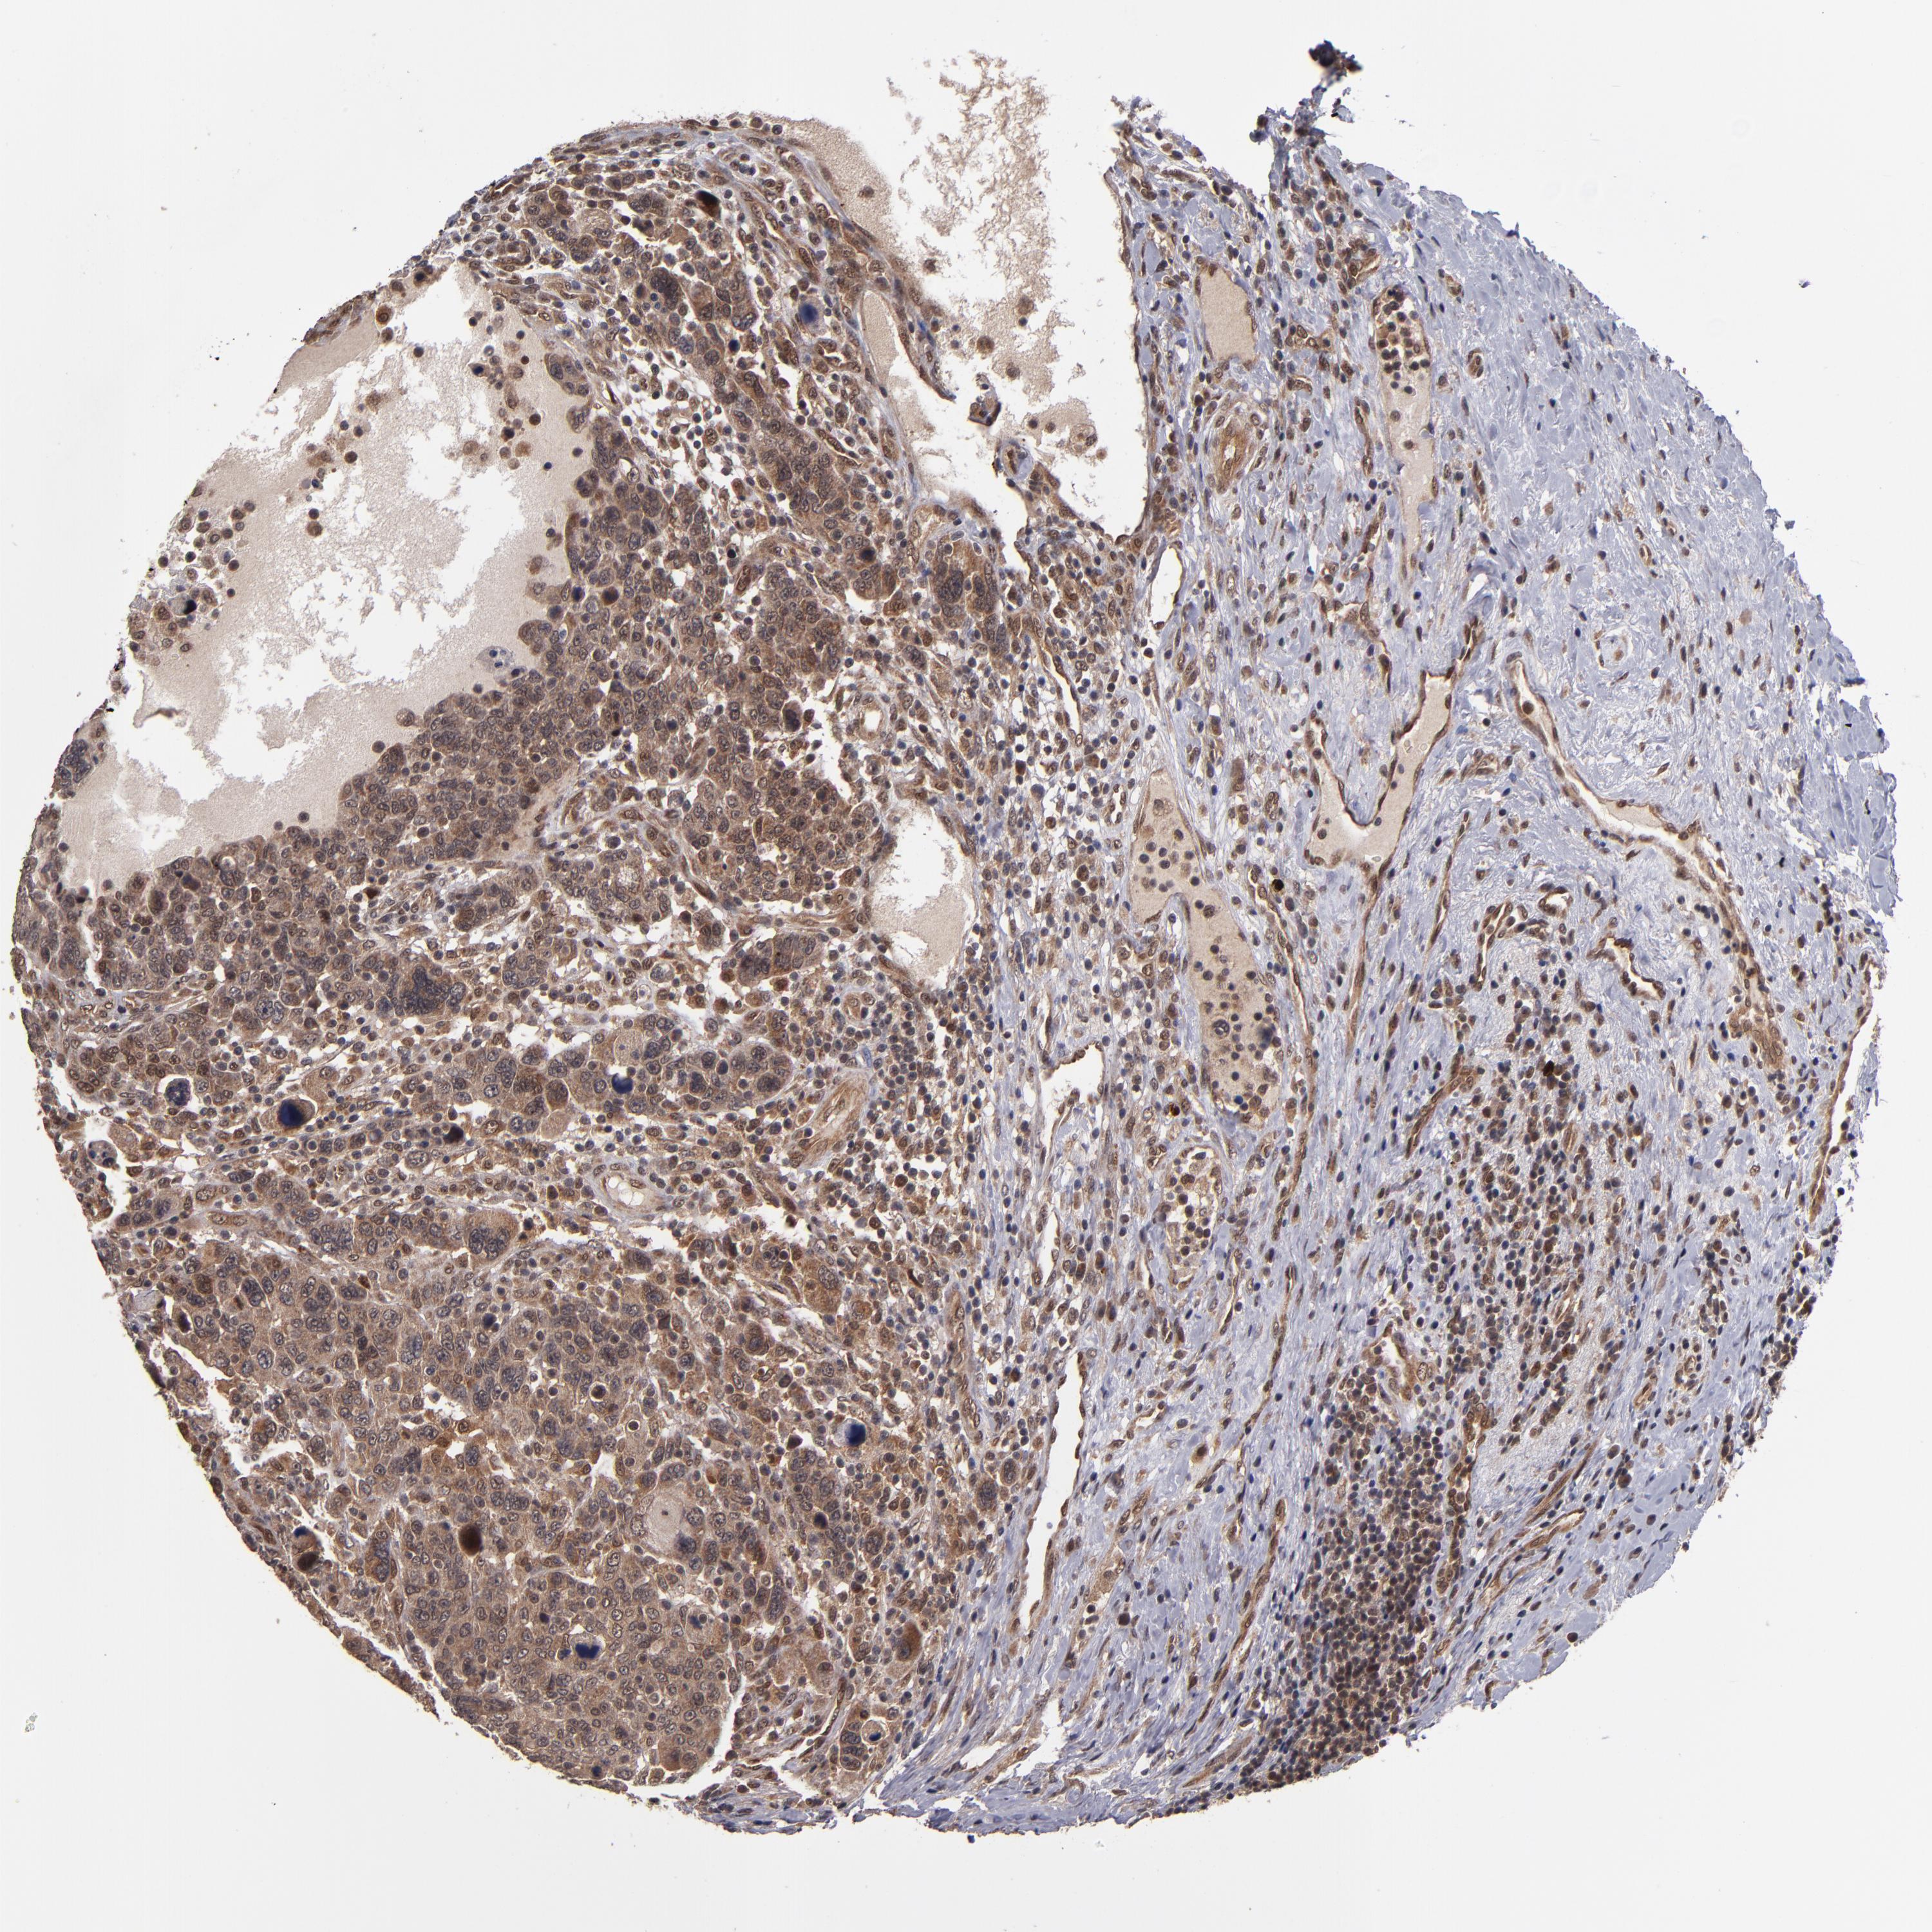

BRCA TCGA BRCA VALIDATION PROTEIN EXPRESSION